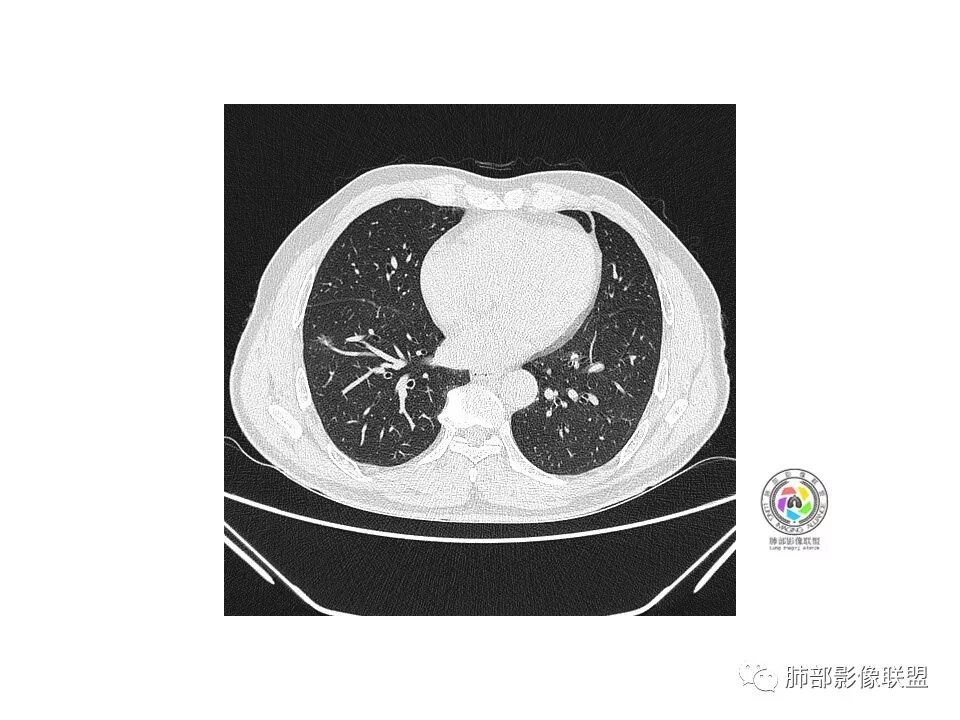

右肺下叶见边界清晰混合磨玻璃密度影,目测内见实性结节小于5mm,有浅分叶,前缘小叶间隔阻挡,月牙铲?胸膜牵拉,老年患者,MIA可能,鉴别炎性病变,抗炎后复查

患者老年男性,以咳嗽 、咳痰3天就诊,胸CT:右肺下叶前基底段mGGO,内可见血管形态改变,细支气管扩张,病灶边界清,边缘可见月牙铲。考虑恶性,腺癌?但建议先抗炎治疗后复查

老年男性、咳嗽咳痰三天,右下前基底段GGN,血管影增多,伴类似的树芽,边缘稍模糊,考虑结核。

右肺下叶磨玻璃结节,密度不均,边缘收缩,胸膜牵拉,考虑炎性,建议复查,除外腺癌。

右肺下叶混合磨玻璃结节,边缘清晰,浅分叶,月牙铲,胸膜牵拉,血管进入,考虑MIA可能,鉴别炎性病变

磨玻璃结节,边缘清楚,浅分叶,月牙铲,考虑腺癌可能,抗炎后复查。

右肺下叶混合磨玻璃密度结节影,局部胸膜牵拉,月牙铲,考虑腺癌

磨玻璃小结节,有明显收缩性表现,胸膜凹陷,考虑腺癌

患者老年男性,咳嗽  咳痰3天就诊。胸部CT:右肺下叶前基底段混合磨玻璃结节,边缘清楚,可见毛刺、胸膜牵拉、血管集束、月牙铲征象。综合考虑微浸润腺癌可能大。

右肺下叶前基底段混合磨玻璃结节,边界清,浅分叶,胸膜牵拉,月牙铲,血管进入,考虑:微浸润腺癌可能性大,抗炎后复查。

老年男性,右下叶孤立ggo,先抗炎2-3周复查,无变化→切,小了→炎性

40岁以上男性,孤立混合磨玻璃,边界清楚,分叶,胸膜凹陷,血管集束、穿行,考虑腺癌。

右肺下叶孤立混合磨玻璃结节,隐约细小毛刺,似有月牙铲,胸膜稍牵拉,考虑MIA(微浸润腺癌)可能,常规飞一下。

右肺下叶前基底段混合磨玻璃密度结节 边缘见月牙铲 部分边缘清 部分似清非清 远端见磨玻璃片影,炎性和粘液腺癌鉴别 先抗炎复查

老年男性,咳嗽、咳痰3天。胸部CT:右肺下叶前基底段mGGN,边缘清楚,内可见不规则实性成分,病灶可见空泡、毛刺、胸膜牵拉、血管集束征象。考虑MIA可能大,抗炎2W后复查。

老年男性,右下肺前基底段混合GGN,边缘清晰,月牙铲,叶间胸膜牵拉,有轻度收缩力。结合病史抗炎2-3周后复查,消失考虑炎症,变化不大为腺癌。本例总体支持腺癌

老年男性,咳嗽3天,右肺下叶前基底段混合磨玻璃结节,形态不规整,相邻胸膜凹陷,可见血管影,考虑腺癌可能性大,不除外炎症可能,建议抗炎1~2周,1个月复查胸部CT。

右肺下叶mGGN,内部结构紊乱,可见小点状高密度影,边缘清晰,小叶间隔阻挡,轻度收缩力,考虑MIA,常规飞一会20天复查。

右肺下叶磨玻璃影,边界似清非清(考虑部分为血管断面围绕),周边见条索灶,胸膜牵拉弱。我把炎症放前面,建议抗炎治疗后复查除外恶性。

老年男性,右肺下叶前基底段GGN,界清,内部血管结构杂乱,叶间胸膜牵拉。考虑恶性,早期腺癌可能,建议抗炎治疗后复查对比。

右肺下叶前基底段见一磨玻璃结节影,呈分叶状,边缘部分模糊,与胸膜间有长条索粘连,内有增粗的血管影,后者边缘毛糙,考虑微浸润性腺癌,建议抗炎治疗后复查

老年男性,右肺下叶前基底段斜裂旁可见单个混合型磨玻璃结节mGGN,边缘清,内部结构紊乱,进入的血管增粗,支气管关系不好判断,斜裂侧可见牵拉,常规考虑微侵腺癌MIA,建议先抗炎后复查及手术干预。

老年男性,咳嗽咳痰3天。MGGN,边缘见月牙铲、胸膜牵拉,血管移动联通?冠状位隐约可见支气管穿行,考虑MIA,重建冠位可见结节比较靠近叶裂,可积极手术处理。

老年男性,右S8混合磨玻璃结节,边缘尚清晰,局部凹陷,叶间胸膜牵拉,考虑MIA可能大,建议抗炎治疗10天,6-8周后复查

右肺下叶混合磨玻璃密度结节,有月牙铲,内可见血管,血管移动联通,常规消炎复查,还存在考虑AIS-MIA

患者老年男性,右下肺前基底段靠近胸膜侧可见一个mGGO结节,边缘清淅,可见分叶征及月牙铲,小结节病灶胸膜牵拉明显,首先考虑MIA可能性大。

右肺下叶mGGO,边缘清晰,浅分叶,内血管影增粗,见点状实性成分,小支气管牵拉扩张,考虑MIA,建议抗炎后复查。

右肺下叶前基底段mGGN,边界清晰,内部结构杂乱,见网格空泡感,月牙铲,浅分叶及胸膜牵拉,倾向MIA。

右肺下叶GGO,边缘清晰,有月牙铲,有血管进入,内部结构紊乱,胸膜牵拉,考虑MIA,常规建议抗炎治疗后复查。

右肺下叶磨玻璃结节,边界清晰,边缘有分叶及月牙铲,并可见轻度胸膜牵拉,收缩力弱,有血管移动联通征,而且病灶内血管影轻度增粗,实性成分很少,考虑AIS,可以让子弹再飞一会,或常规抗炎治疗后复查。

界清ggo,月牙铲,考虑腺癌

右肺下叶前基底段磨玻璃小结节,其内血管稍增粗,边缘见分叶、月牙铲,考虑ais,炎性结节不排